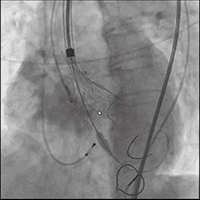

● 更换新瓣膜跨瓣后,猪尾难以送至无冠窦底,故行造影定位窦底。

隐约可见“无冠窦”后部更深窦底,位于“无冠窦”下约6mm,参考该位置后进行0位定位,无起搏逐步释放至工作位,瓣膜无明显位移表现,瓣膜形态压缩良好,造影评估无反流。准备释放瓣膜。

无张力释放,脱钩后瓣膜略微下滑,约位移瓣环下4~5mm位置,瓣膜整体形态良好,造影评估无可见反流。

超声评估,微量瓣周反流,二尖瓣工作良好,植入位置理想。

结束手术,一波三折终成功!